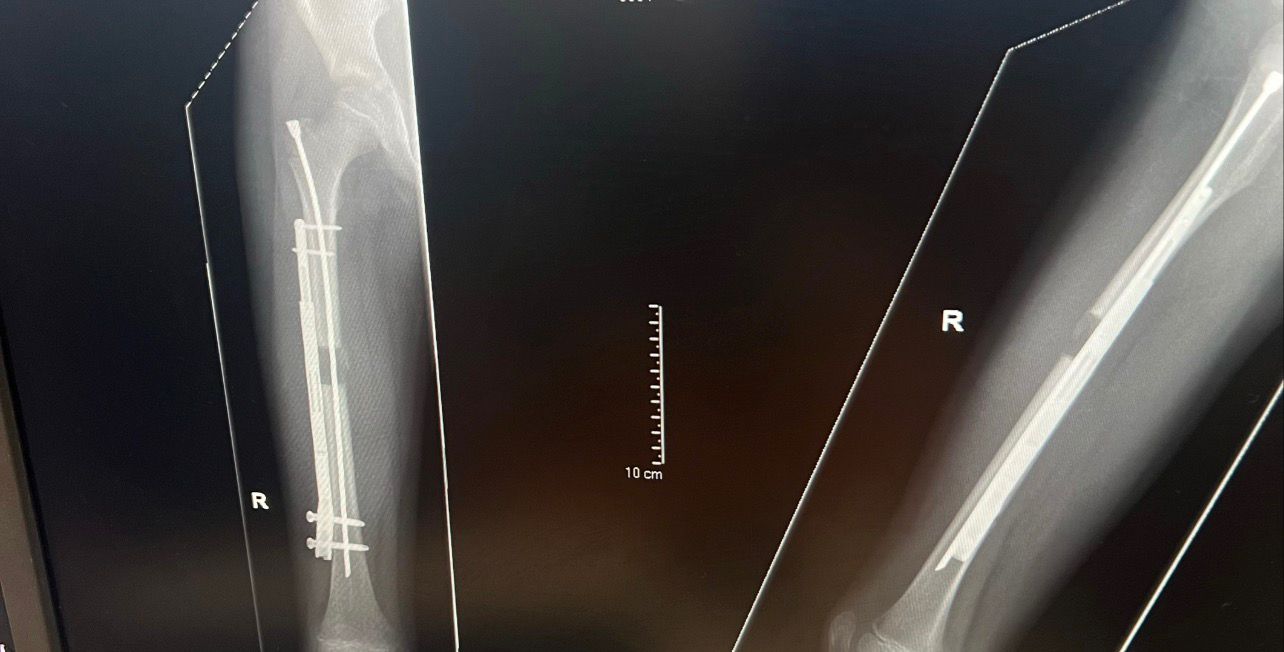

Experts implanted a lengthening nail on the surface of Alfie’s right thigh bone, which was slowly pulled apart over time using magnets to help him gain 3cm.

The new method, developed in the US, involved placing a lengthening nail – known as a motorised telescopic nail – on the surface of Alfie’s femur, the long bone in the thigh.

The bone is surgically cut, with a rod placed down the middle to keep it straight.

To make the limb longer, a magnetic device was placed on Alfie’s leg three times a day for a month.

This process helped the nail slowly pull the two bone ends apart – by around 1mm each day – while the body naturally filled the gap with new bone tissue.